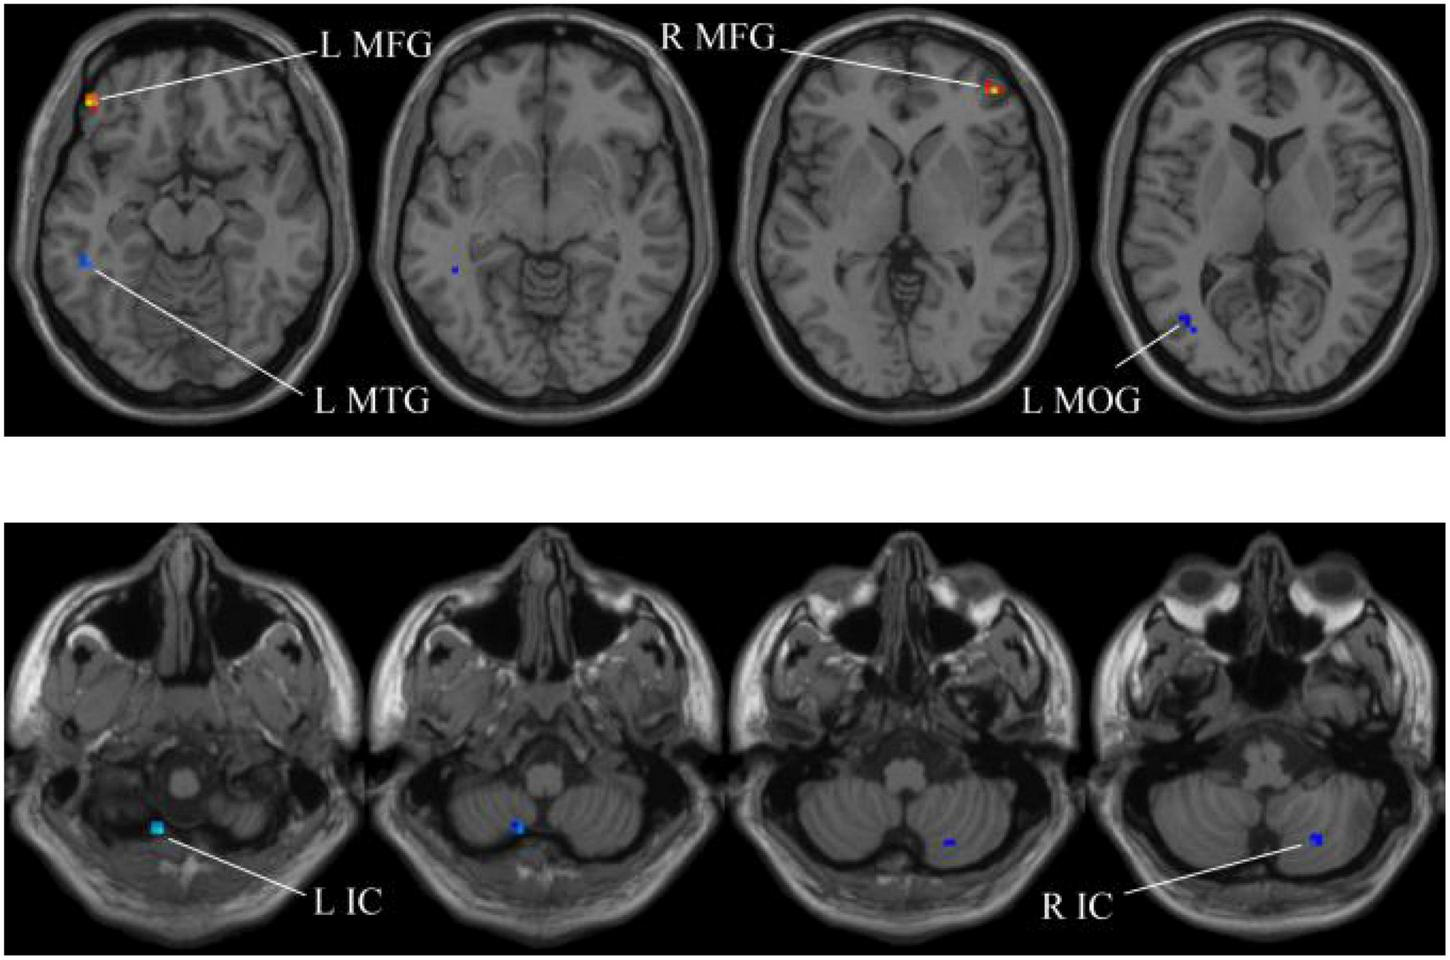

In our experiments, the MGS-WBC model is adopted in two whole-brain structures, including ReHo and ALFF, to reduce the data redundancy and extract multiscale features. For the whole-brain structure calculated by ReHo, as shown in Table 1 and Figures 4, 5, we obtain 10 obvious regions of the brain using MGS-WBC model, including the right gyrus rectus (GR), left pallidum (PAL), left cingulate gyrus (CG), left supplementary motor area (SMA), left inferior cerebellum (IC), right IC, left middle temporal gyrus (MTG), left middle frontal gyrus (MFG), right MFG, and left middle occipital gyrus (MOG), while only six obvious brain regions, namely, left IC, right IC, left MTG, left MFG, right MFG, and left MOG, are found using a single significant threshold (two-sample t-test, p < 0.001). Significantly, each significant region is composed of the activated voxels in the brain. Then, the features extracted from 10 significant regions and six significant regions are separately employed as the input of classifiers, including NB, LDA, LR, and SVM, to evaluate the aMCI’s diagnostic performance. Table 2 presents the diagnostic performance of aMCI using different feature extraction methods of the whole-brain structure (ReHo). The results of MGS-WBC2 all exceed 66.67% in the four classifiers. Besides, compared with the single significant threshold in the whole-brain structures (SSW1) (Zhang et al., 2015; Yang et al., 2018), the results of MGS-WBC3 provide the ACC of 88.06, 89.55, 91.04, and 91.04% in the four classifiers, improving by 4.48, 2.98, 10.44, and 4.47%, respectively. Concurrently, the AUC are 94.12, 96.08, 96.88, and 95.72% in four classifiers, and the increases are 2.24, 1.96, 5.53, and 1.51% compared with SSW1. For F1-Score, we provide about 87.88, 89.55, 91.18, and 90.91% in four classifiers, and maximum improvements are 4.30, 2.23, 9.49, and 3.95% compared with SSW1.

The extracted clusters using MGS-WBC model after ReHo calculation.

The x, y, and z coordinates are the primary peak locations in the MNI space. Cluster size ≥ 5 voxels in two-sample t-test. L, left; R, right; GR, gyrus rectus; PAL, pallidum,; CG, cingulate gyrus; SMA, supplementary motor area; IC, inferior cerebellum; MTG, middle temporal gyrus; MFG, middle frontal gyrus; MOG, middle occipital gyrus.

FIGURE 4

Compared with the HC group, the ReHo in aMCI group exhibits prominent differences based on MGS-WBC2. L, left; R, right; GR, gyrus rectus; PAL, pallidum; CG, cingulate gyrus; SMA, supplementary motor area.

FIGURE 5

Compared with the HC group, the ReHo in aMCI group exhibits prominent differences based on SSW1. L, left; R, right; IC, inferior cerebellum; MTG, middle temporal gyrus; MFG, middle frontal gyrus; MOG, middle occipital gyrus.